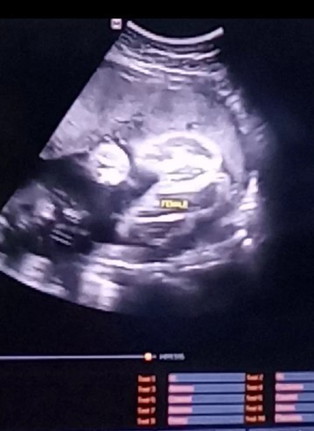

28+3วีค

มองออกมั้ยค่ะว่าผู้ชายหรือผู้หญิง

ในภาพบอกผู้หญิงนะคะ 7 เดือนแล้ว โอกาสผิดพลาดต่ำมากค่ะ